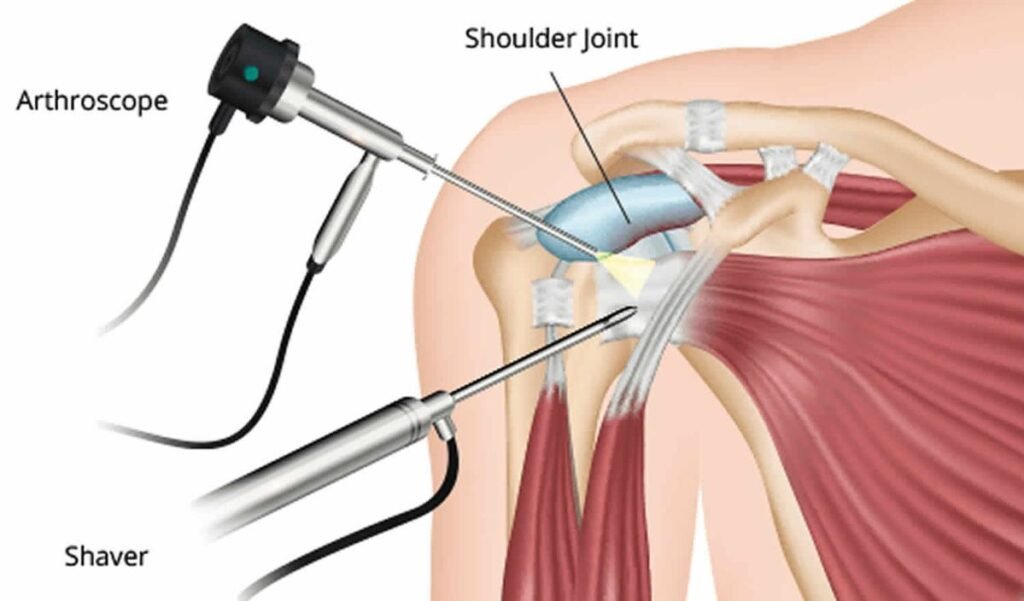

Arthroscopy is a minimally invasive surgical procedure used to both diagnose and treat joint problems. During the procedure, a small camera called an arthroscope is inserted into the joint through tiny incisions. This provides the surgeon with a clear, magnified view of the joint’s internal structures, allowing precise assessment of cartilage, ligaments, and other tissues. Using specialized instruments, the surgeon can then repair or remove damaged tissues, treat inflammation, or correct structural issues—all while minimizing trauma to surrounding muscles and tissues. Arthroscopy typically results in less pain, reduced scarring, faster recovery, and shorter hospital stays compared to traditional open surgery. It is commonly used for joints such as the knee, shoulder, ankle, hip, and wrist.